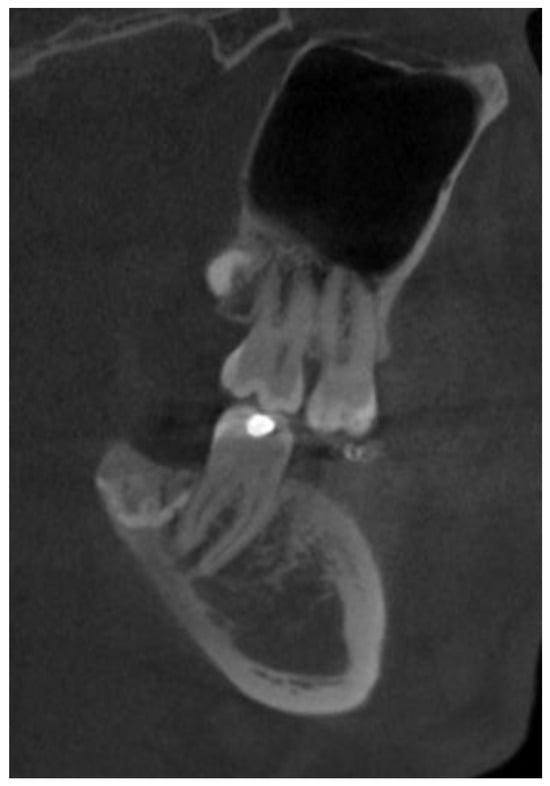

The patient was a generally healthy male without any history of surgery, illness, or surgery in the oral cavity region. The occurrence time of this lesion and its growth duration were not established. All of the surrounding anatomical areas and spaces were free of any diseases. Routine panoramic radiography (panx) and cone-beam computed tomography (CBCT) excluded any major changes in the bone near the tumour and excluded any potential odontogenic cause of the MRT swelling. The cortical parts of the bone in the CBCT study were also normal. No bone erosions, infiltrations, tooth resorptions, or bone swelling were detected (Figure 3). Because of the lack of substantial bone involvement, except for the impacted right mandibular wisdom molar with visible signs of bone ankylosis, suspicion of a nonodontogenic tumour was established.

Because of the lack of clear margins after the excisional biopsy and the presence of some of the retained wisdom teeth, a decision was made to radicalise the first procedure. The main focus was to maintain good soft tissue margins, and the remaining wisdom teeth were removed, followed by the use of an osteoalveoplasty procedure. Control CBCT and panx evaluation revealed that the bone and tooth status after the first procedure was good and that the patient had healed properly (Figure 4, Figure 5 and Figure 6).

After one and two weeks, healing was uneventful. Because of the loss of sensation in the lower lip caused by inferior alveolar nerve damage (IAN), an additional course of 0.32 mg Neurovit was administered two times per day for fifty days in total (1 tabl. consisting of 100 mg wit. B1, 200 mg wit. B6, 0.2 mg wit. B12; 100 tabl.; G.L. Pharma, Gerot-Lannah, Wien, Austria). After the second dose of pharmacological treatment, the overall numbness of the lip decreased; however, full lip function was still not restored. After three years, some degree of lip numbness remained; however, there was no recurrence of the SC tumour. Because of the proximity of part of the ankylotic crown of the right wisdom molar, a part of the teeth remained in the bone and was symptomless both clinically and during routine radiological CBCT evaluation (Figure 7, Figure 8 and Figure 9). The scope of paraesthesia decreased slightly over the years, but the scope of missing function was not troublesome for the patient.

Figure 8. Cone-beam computed tomography with visible remnants of a fully retained crown of the lower wisdom teeth. No osteolytic, cystic, or inflammatory changes are visible in the bone or adjacent structures. The inferior alveolar nerve is visible in close proximity to the dental crown remnants.

Figure 9. Cone-beam computed tomography after three years in the sagittal plane showing good healing of the bone superiorly placed from the remnants of the molar crown. Adjacent second molars and adjacent bone without any radiological changes in their structure.